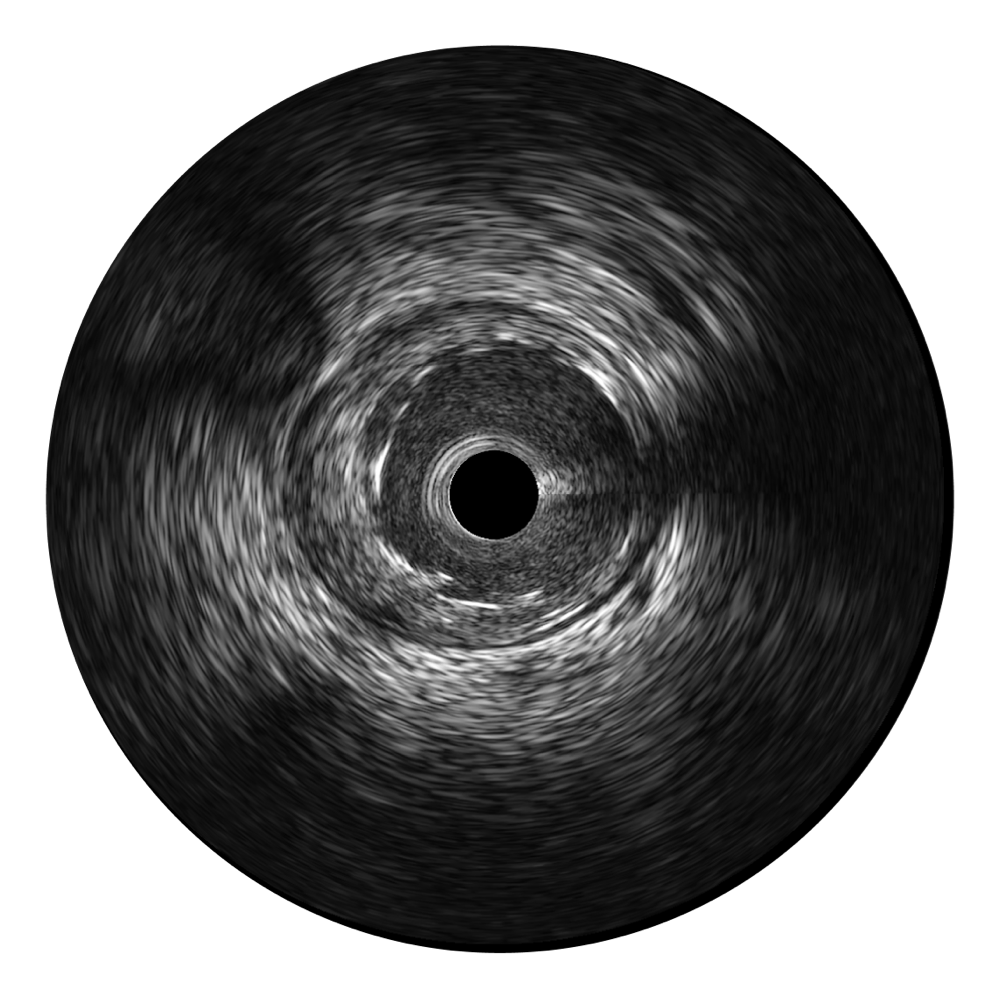

• 传统IVUS图像

对比传统IVUS导管成像,美狮贵宾会官网宽频IVUS图像的近场支架梁显影更细腻,远场中膜外血管仍清晰可辨,兼顾远中近,兼顾分辨力与穿透深度